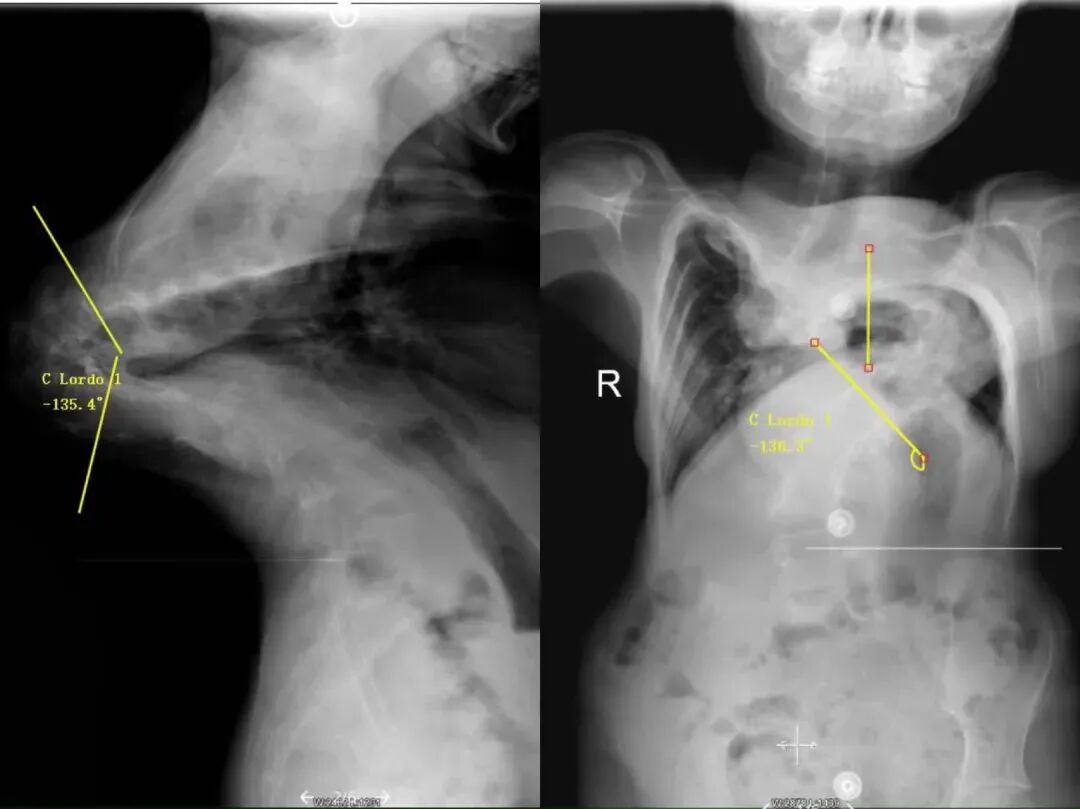

纠缠家坪多年的“怪病”也终于现形:

重度先天性侧凸和后凸脊柱畸形

• 侧凸角度 135 度

• 后凸角度 138 度

• 一半以上的胸椎椎体有超过90度的严重旋转

经过4个月的牵引治疗,家坪的脊柱肉眼可见在变好:

• 后凸角度从138度减少到 70

• 侧凸角度从135度减少到 51

• 身高也从131cm上升到 153cm